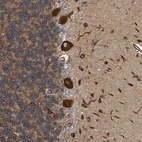

Immunohistochemical staining of human cerebellum shows strong cytoplasmic positivity in Purkinje cells.